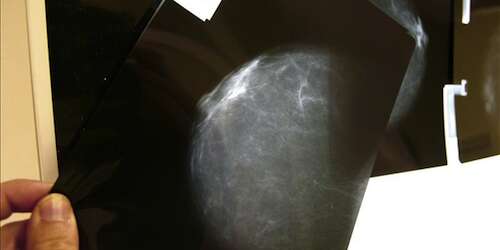

Pero eso cambió el día en el que casi sin querer, solo porque sí, le pregunté a mi papá durante una llamada telefónica ‘what’s up?’. Él pensaba que yo sabía algo, pero en realidad no sabía nada. Y él me habló de mi madre, de unos exámenes, de una masa pequeña, del seno izquierdo, de cáncer… En un minuto pasé de la alegría de la recién casada al espanto de quien escucha ‘tu mamá’ y ‘cáncer’ en una misma oración. La boca entreabierta, como ahogada, sin poder emitir un sonido, una palabra… Solo las lágrimas bajando desesperadamente y sin control por mis cachetes, mojando el teclado de la computadora que tenía en la falda.

Cada vez que visito la casa de mis padres en Caguas, noto la cicatriz que quedó sobre el pecho de mi madre, una herida que le hicieron para poder introducir los químicos en su cuerpo. Esa cicatriz me recuerda una lucha ganada, pero es también el recordatorio de una enfermedad hereditaria …